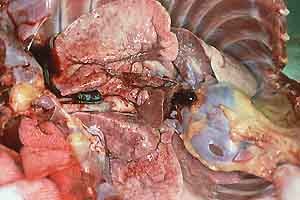

- Case 23-1. Gross Images. Lungs (b) have a pale tan

mottling. Cut section of the fixed lung (c) contains diffusely

distributed pale tan 2-3mm foci. Within the white matter of the

brain (d) is an 0.3x1.0cm cavitating lesion.

- Gross Pathology: At necropsy the carcass appeared

in good condition. There was moderate scrotal and inguinal edema.

The lungs were diffusely hyperinflated and did not collapse when

the thoracic cavity was opened. The lungs were gray to white

and had pleural vascular distension and a granular texture throughout

with disseminated firm nodules, ranging in diameter from 1 to

5 mm. The right middle lung lobe was firm and dark red. The spleen

contained a 1 cm in diameter firm, pale-yellow irregular nodule.

There was minimal, focal, gastric ulceration and hemorrhage.

The right cerebral frontal lobe and left occipital lobe each

had 1 cm x 2 cm x 2 cm abscesses.